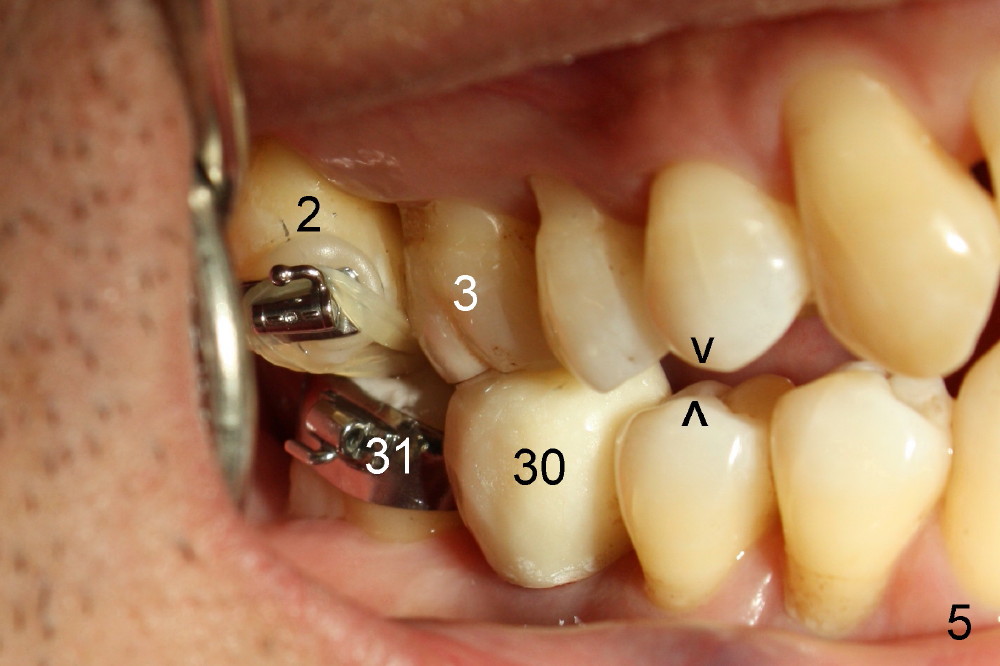

A molar band is placed for #31 and a bracket for #2 (Fig.5). A temporary crown (#30) is cemented with an intention to raise the occlusion. Notice the space between upper and lower premolars (between 2 arrowheads). There is also a space between #2 and 31. One to three elastic bands are placed between the buccal hook of #2 and the lingual cleat of #31 (Fig.5,6). One months passes without correction of the molar cross bite. More bands and brackets are placed in the upper and lower right posterior sextants (Fig.6). With combination action of elastics and segmental wires, the inclination of the tooth #31 is not only corrected buccolingually (blue arrow), but also mesiodistally (black arrow, uprighting). The implant crown is mainly used as an occlusal stop; because of constant wear, composite is being added (*) to its occlusal surface of the temporary crown to keep posterior occlusion open (let #2 and 31 move freely). In this case the implant is in fact not used as a pure anchorage to distalize #31 due to difficulty in placing an open coil spring between #30 and 31 tubes. The alignment of the upper right sextant improves under the tension (bending) of the wire (Fig.7 white arrowhead). The tooth #2 is being moved lingually. In fact, elastics are also placed between #3 lingual cleat (yellow arrowhead) and #30 buccal hook to improve #3 buccolingual position and/or inclination (compare Fig.4 and 7).